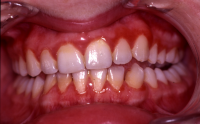

Akut inflammatorisk destruktiv sjukdom i gingiva och parodontium.

Karakteriseras av approximala nekrotiska och fibrintäckta sår (nedsmälta papiller) som är smärtsamma vid beröring och mycket lättblödande.

Patienten kan ha påverkat allmän tillstånd och ofta foeter ex ore.

I anamnesen förekommer ofta kombination av nedsatt immunförsvar, rökning, stress och dålig munhygien. HIV/Aids kan finnas som bakgrundsfaktor.